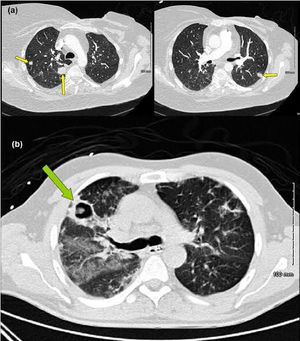

ALLERGIC BRONCHOPULMONARY ASPERGILLOSIS (ABPA) OVERVIEW Allergic Bronchopulmonary Aspergillosis (ABPA) is an allergic or hypersensitive reaction to a fungus known as Aspergillus fumigatus. This is a fungi found in the soil. Although most of us are frequently exposed to Aspergillus, a reaction to it is rare in people with normal immune systems. However, in certain people, the immune system overreacts to the antigens of Aspergillus fumigatus found in the lungs. This may damage the airways and result in permanent lung damage. ABPA most commonly affects people with asthma or cystic fibrosis. Many people with ABPA also suffer from allergic conditions such as atopic dermatitis (eczema), urticaria (hives), allergic rhinitis (hay fever) and sinusitis. SYMPTOMS & DIAGNOSIS Symptoms If you have asthma, the first noticeable symptoms of ABPA are usually progressive worsening of your asthma symptoms such as wheezing and shortness of breath. Other symptoms of ABPA include: • Cough with brownish flecks or bloody mucous • Fever • General weakness or malaise Diagnosis Diagnosis for ABPA is determined by health history, x-rays or CT scans, allergy skin testingand/or blood tests. TREATMENT & MANAGEMENT The fungus that causes a reaction is difficult to avoid, so medication is typically prescribed to manage ABPA. Asthma medications such as oral corticosteroids open the airways and make it easier to cough and clear out the fungus. The use of this medication depends upon the individual and the severity of ABPA. The prescription for some people is to take the medication when they have symptoms. Other people with more severe cases of the disease may require daily corticosteroid therapy. In addition, an oral anti-fungal such as itraconazole may be recommended, although it is somewhat controversial regarding its effectiveness. If you are diagnosed with ABPA, you should be followed closely by your physician in order to prevent or minimize damage to your lungs.